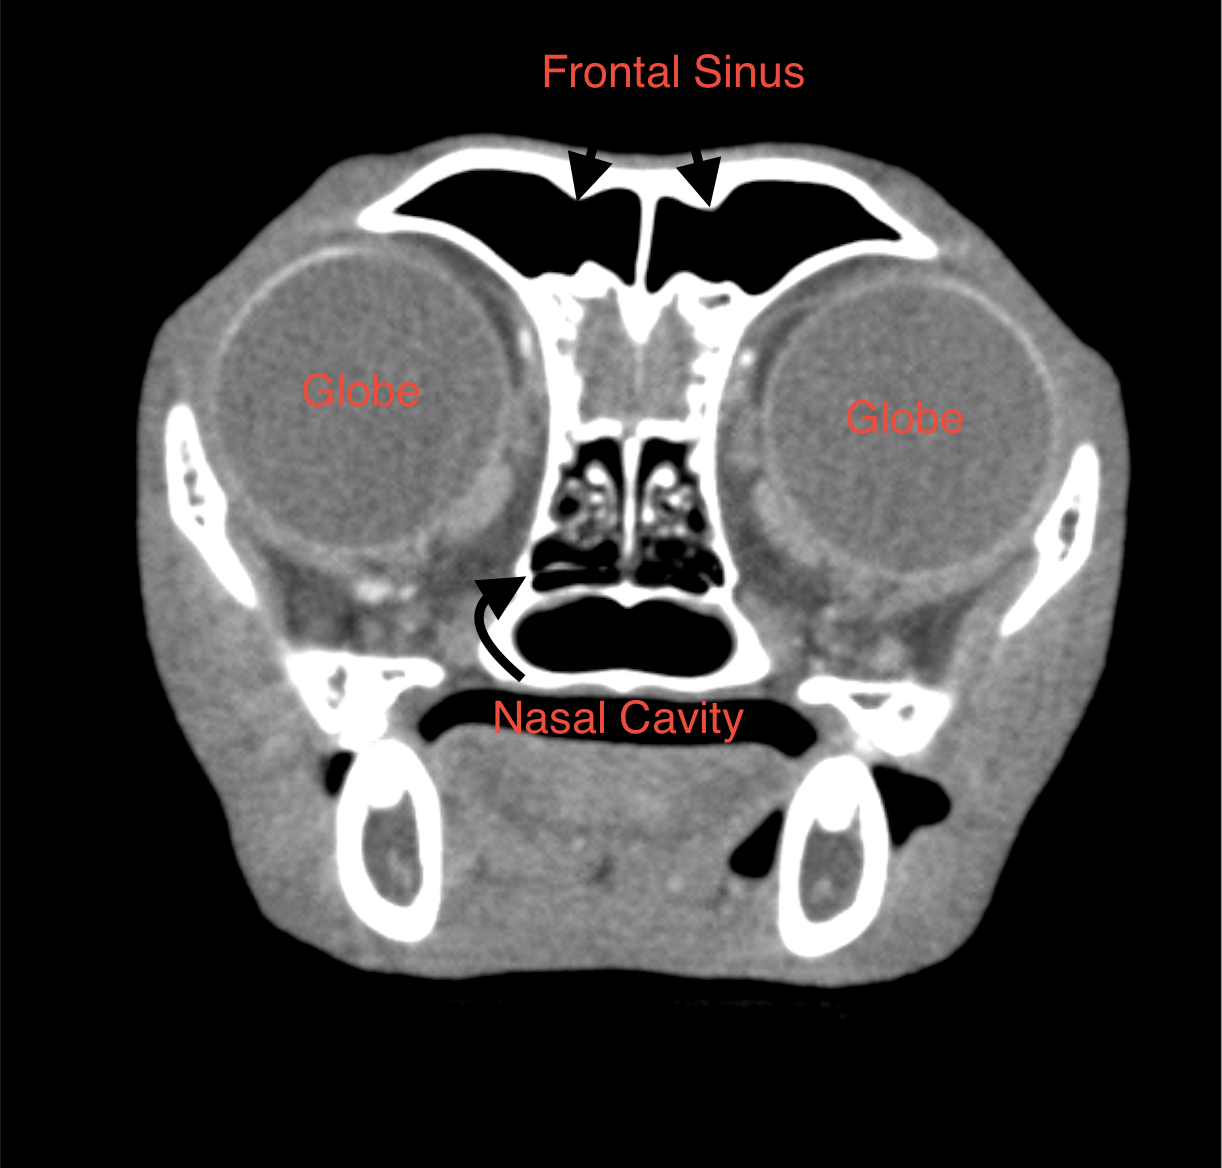

The nasal cavities and frontal sinuses are within normal limits. The oropharynx and nasopharynx are within normal limits. The regional lymph nodes, medial and lateral retropharyngeal are moderately enlarged. The mandibular lymph nodes are within normal limits. The globes, retrobulbar spaces, and brain appear within normal limits.